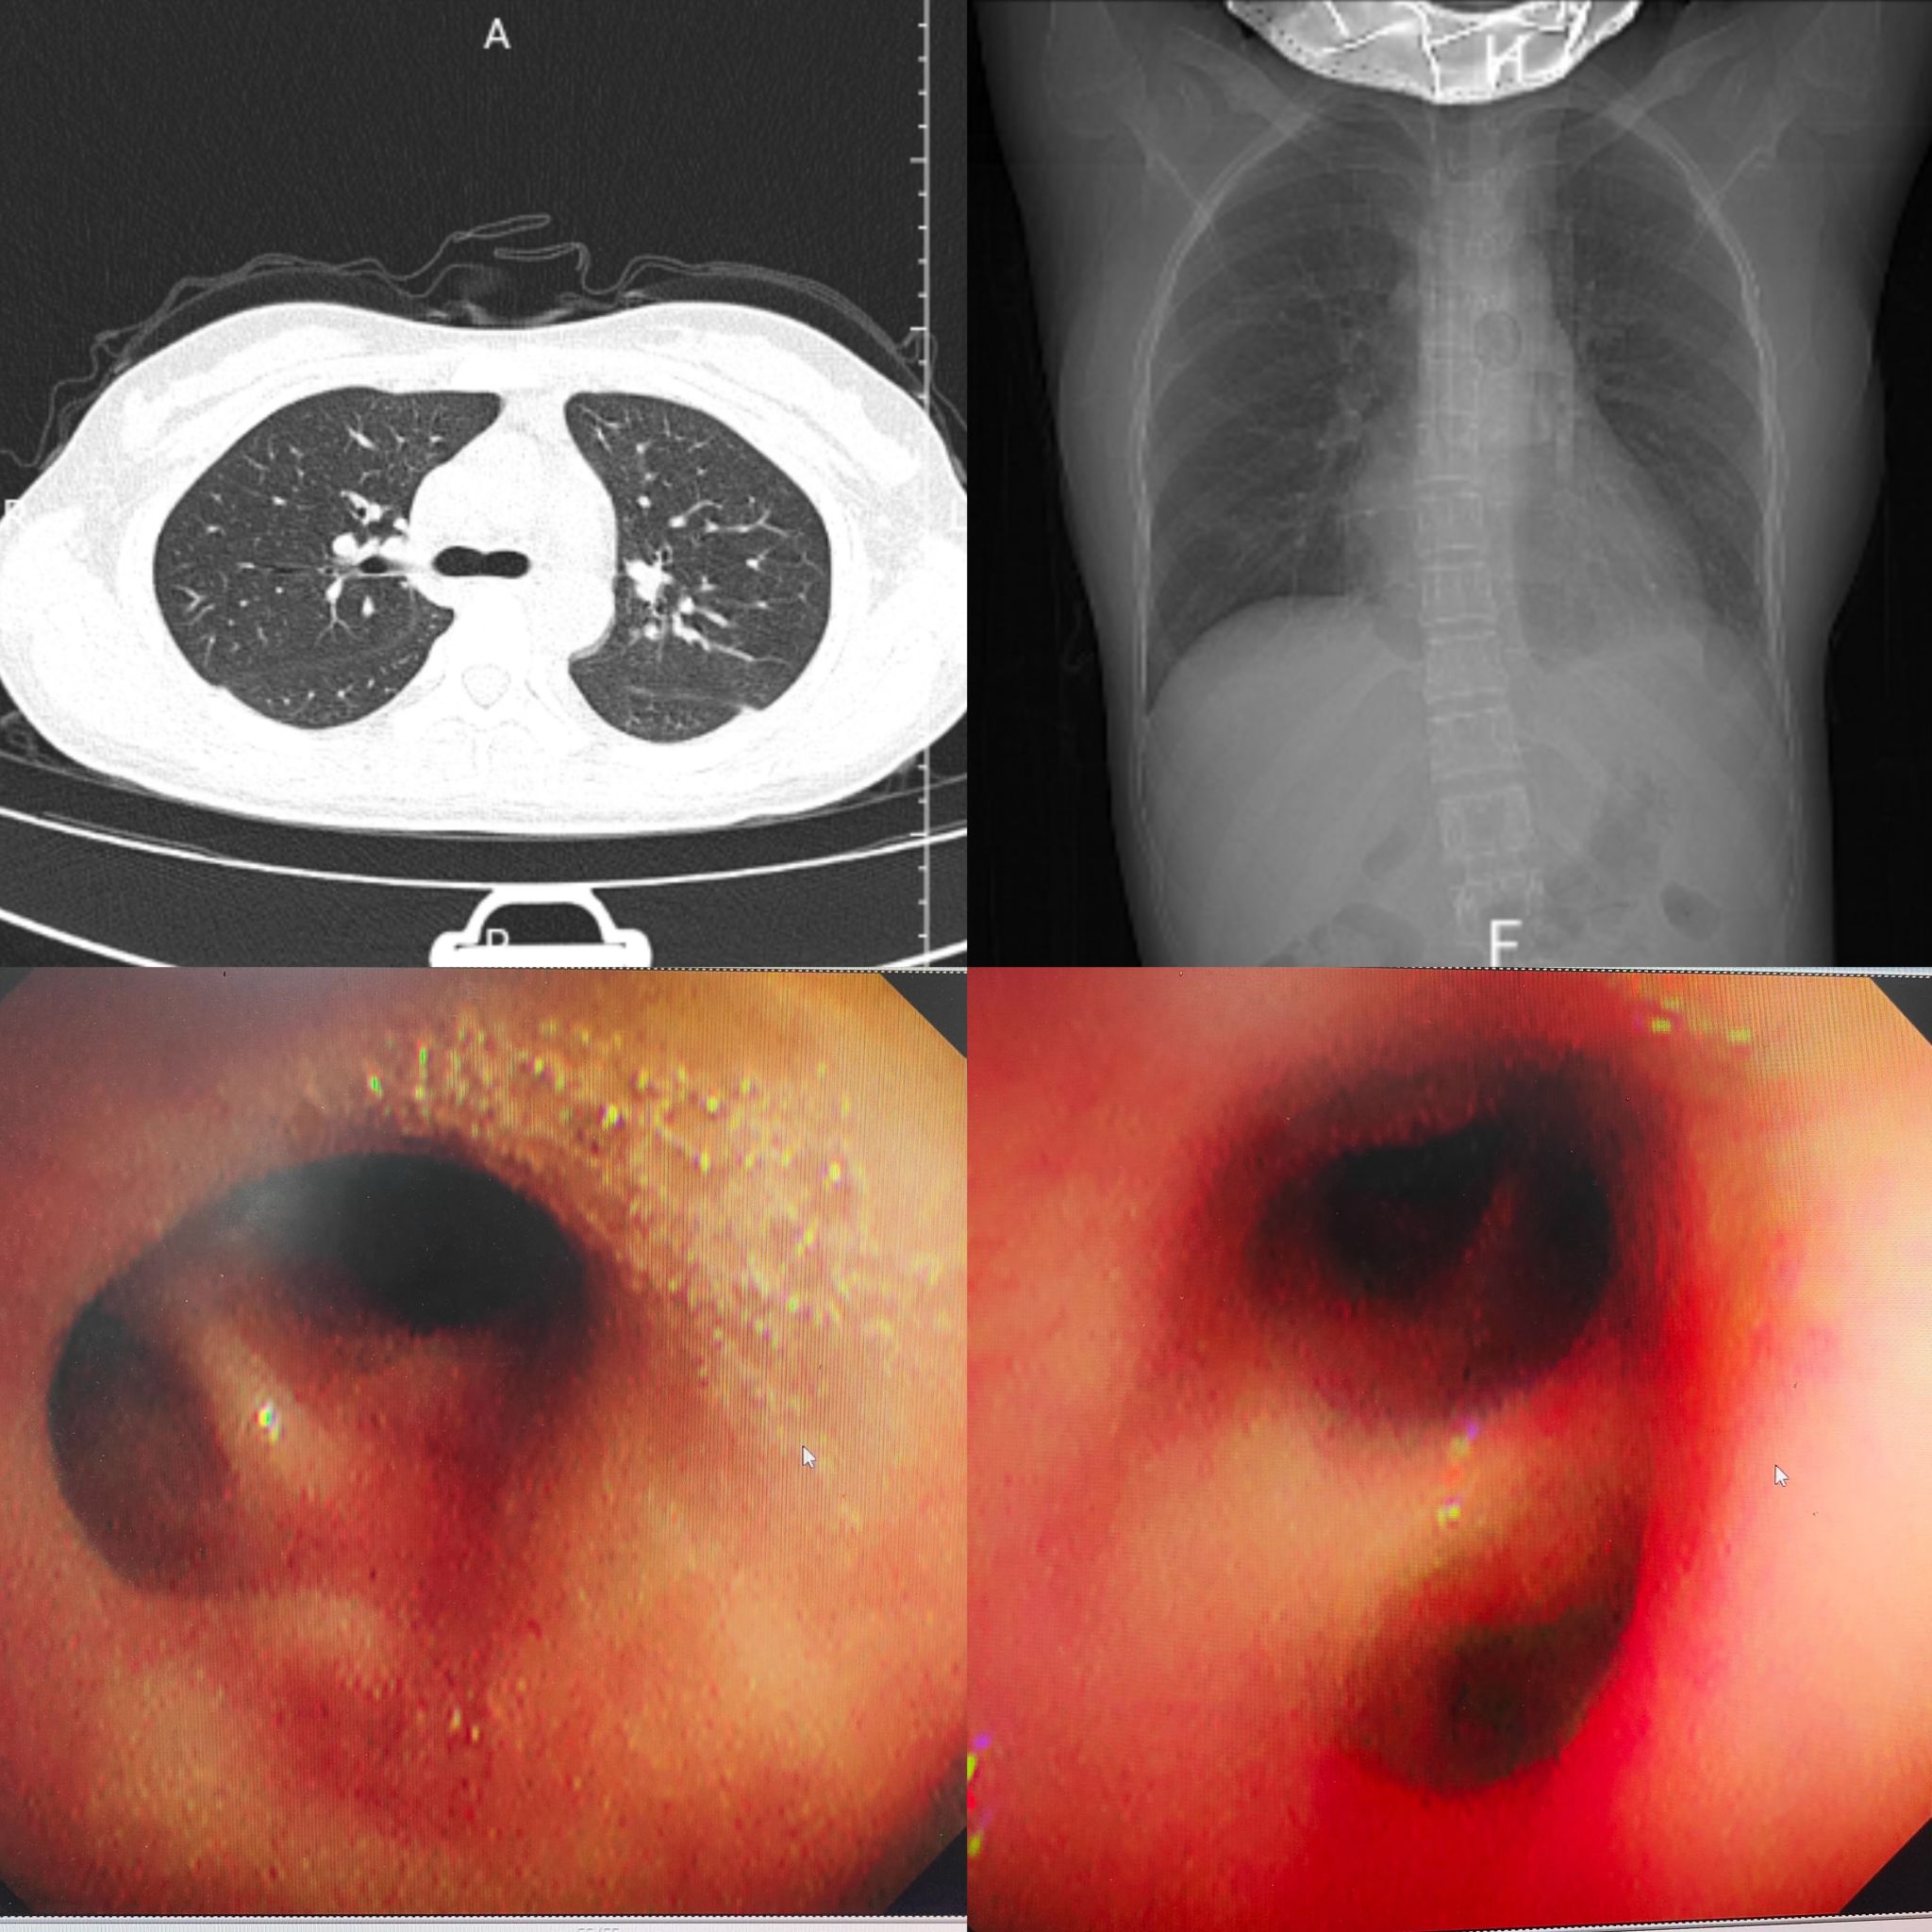

治疗后胸部CT及支气管镜下表现

经过24小时紧急救治,患儿呼吸困难症状逐渐减轻,氧合、凝血指标趋于稳定。36小时体温下降,48小时体温、凝血指标恢复正常,胸片显示胸水及实变明显吸收。120小时复查胸部CT,肺部实变、胸水基本消失。168小时各项指标均达正常水平,后续经中医巩固治疗,顺利出院。出院后,医院将对患儿实行危重症全周期随访管理,持续筑牢生命安全防线。